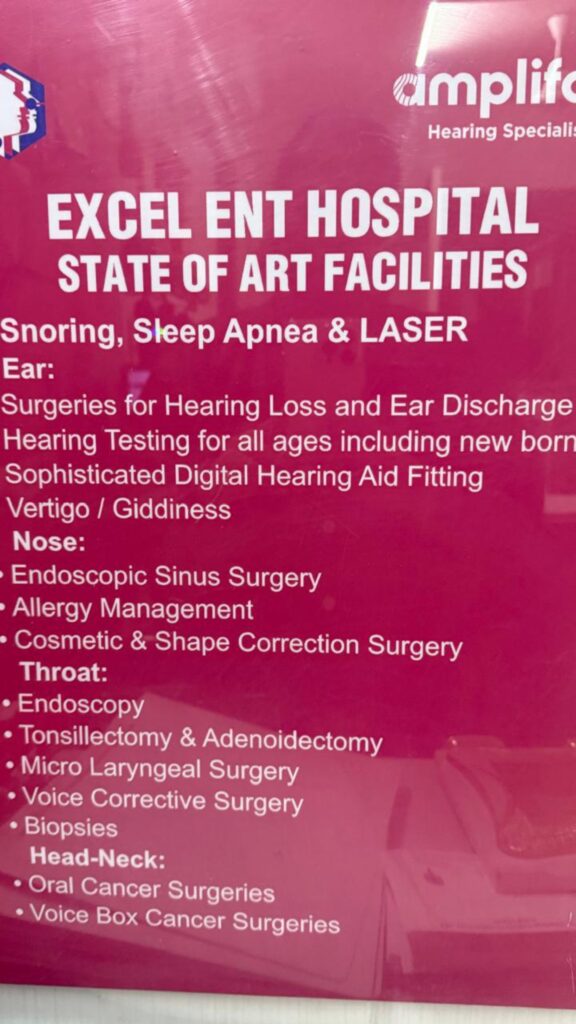

Our Specialized ENT Services

Expert Sinus & Nasal Surgery

Endoscopic solutions for sinus disorders, polyps, and nasal blockages.